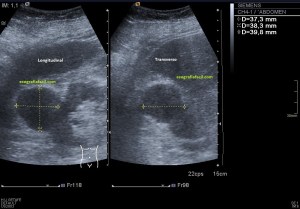

Es muy útil para lesiones que han crecido mucho y no podemos conjugar en una sola imagen, por ejemplo, un lipoma, cuando superan la medida de la huella de la sonda no son medibles, hay que usar «panoramic view», y como este caso, otros muchos.

En la imagen 3 ves una imagen de un lipoma, mide 7 cms, la huella de la sonda mide 5cms, la «panoramic view» posee una regla centimetrada que sigue el contorno de la imagen, justo en la profundidad de la misma y lo marca la flecha amarilla. La profundidad la marca la flecha roja y la flecha blanca marca el rango centimetral de los 5cms, fíjate que la línea blanca es ligeramente mayor cada 5 cms. Sirve de referencia, como en la imagen 4 donde ves una colección en el glúteo de más de 10 cms.

Podemos medir valores superiores a los 15cms con alta calidad de imagen…podemos llegar a medir valores por encima de los 25 cms…es verdad que no todos los equipos tienen este ajuste ecográfico, es decir, es una aplicación y por tanto hay que pagarla.